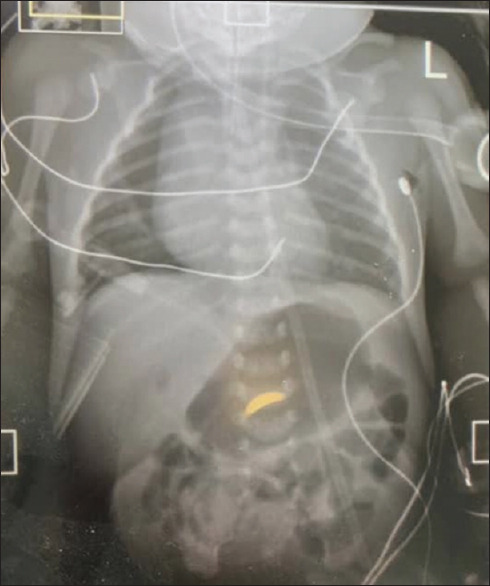

摘要:在尼日利亚和西非次区域,食道闭锁伴气管食道瘘(TOF)的治疗对儿科医生来说无疑是一项非常艰巨的任务,这并不一定是由于缺乏技能,而是由于对新生儿重症监护的巨大需求,而在我们这个地区,重症监护往往缺乏成功所需的基础设施。此外,开胸手术的使用也增加了对新生儿重症监护的需求,导致大量新生儿病情严重,死亡率高。因此,在我们这个次区域,要赶上发达国家对这种复杂病症管理的发展趋势,仍然进展缓慢。自2000年首次成功记录胸腔镜修复伴有TOF的OA后,该技术不断发展和完善,胸腔镜修复术已迅速成为修复所有类型OA(包括长间隙异常)的黄金标准。本文报告了我们在西非次区域首次对两例伴有TOF的OA进行胸腔镜修复的经验。

Abstract: Management of oesophageal atresia (OA) with tracheoesophageal fistula (TOF) in Nigeria and the West African subregion has no doubt been a very demanding task for paediatric surgeons, not necessarily due to lack of skills, but due to the significant demand on neonatal intensive care, which in our region, is often fitted with the poor infrastructure needed to make this a success. Furthermore, the use of open thoracotomy has increased this demand resulting in a significant number having severe morbidities and significant mortality rates. Hence, in our subregion, there is still a slow progression to meet up with the evolving trend of the management of this complex condition in the developed world. Following the first documented successful thoracoscopic repair of OA with TOF since 2000, there has been a progressive evolution and refinement of this technique, such that thoracoscopic repair is fast becoming the gold standard for the repair of all types of OAs, including long-gap anomalies. This article reports our experience with the first two cases of thoracoscopic repair of OA with TOF in the West African subregion.